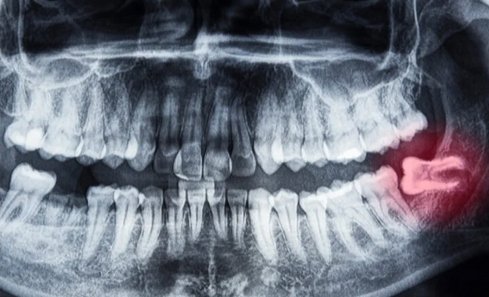

Wisdom Tooth extraction a surgical procedure to remove one or more wisdom teeth , located at the back corners of your mouth on the top and bottom.

• If a wisdom tooth doesn’t have room to grow, results in pain, food entrapment, infection or gum disease, tooth decay infection or other dental problems, you’ll likely need to have it pulled.

• Prevention of potential future problems ,it is recommended for removal if even teeth aren’t currently causing problems.